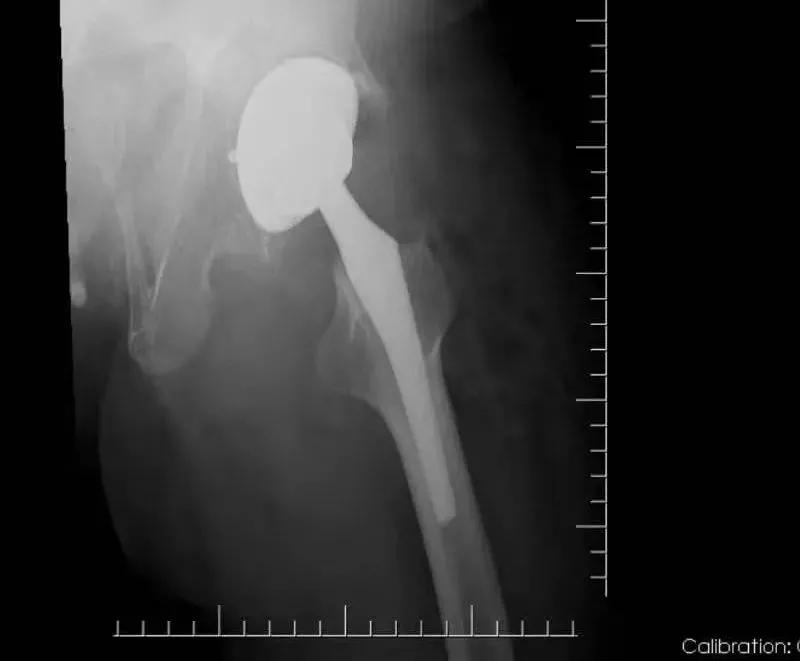

骨一科刘学东主任、黄思聪副主任医师组成手术团队共同为张女士完成了左侧全髋关节置换术、髋关节滑膜切除和髋关节松解术。

髋关节是人体最大的承重关节,对于人的站立、行走、蹲坐等日常活动都非常重要。髋关节置换术被誉为现代关节外科最成功的手术之一,为广大患者提供了最佳的治疗方法。

手术十分顺利!术后,张女士在助行器的帮助下,缓慢行走,原本疼痛的髋关节,也终于不再痛了。 张女士对手术效果十分满意。